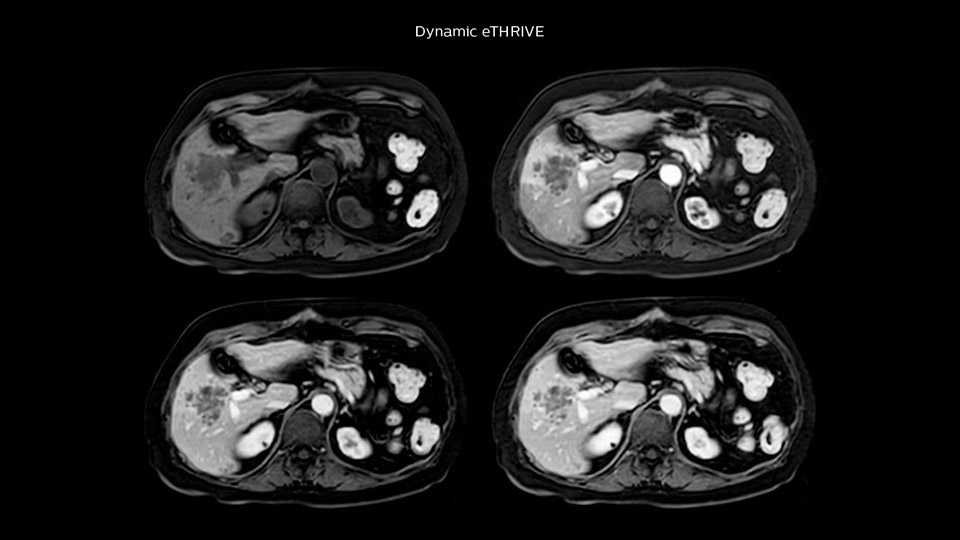

“Our liver exams are quite fast,” says Dr. Baumann. “If the patient tolerates it, we use an arms-up position to reduce the FOV and speed up the exam with dS SENSE.”

“We acquire one transversal high resolution T2-weighted sequence with 3 mm slice thickness, for example for pancreas or liver lesions. Then we also add a T2 fat suppressed MultiVane XD SPIR sequence. We perform these two routinely in our liver imaging. We use high dS SENSE factors to significantly shorten scan times to 2-4 minutes, which can improve our protocol; it’s a very robust scan.”

“We include mDIXON for the dynamic sequences because of the robust and homogeneous fat suppression we get with that. We had been using eTHRIVE, but we are now quite happy with mDIXON. Sometimes we use a medication to calm the bowels, to further improve the image quality.”